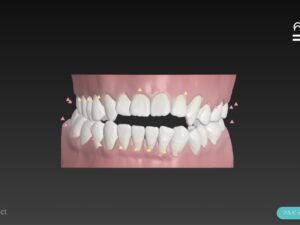

この歯並びが治る原理は

奥歯を上の歯は上に 下の歯は下に押し入れる

あっか という動きをさせて

前歯は上の歯は下に 下の歯は上に引っ張り上げる

ていしゅつ

という動きをさせて矯正終了

🔶アフター🔶

正面